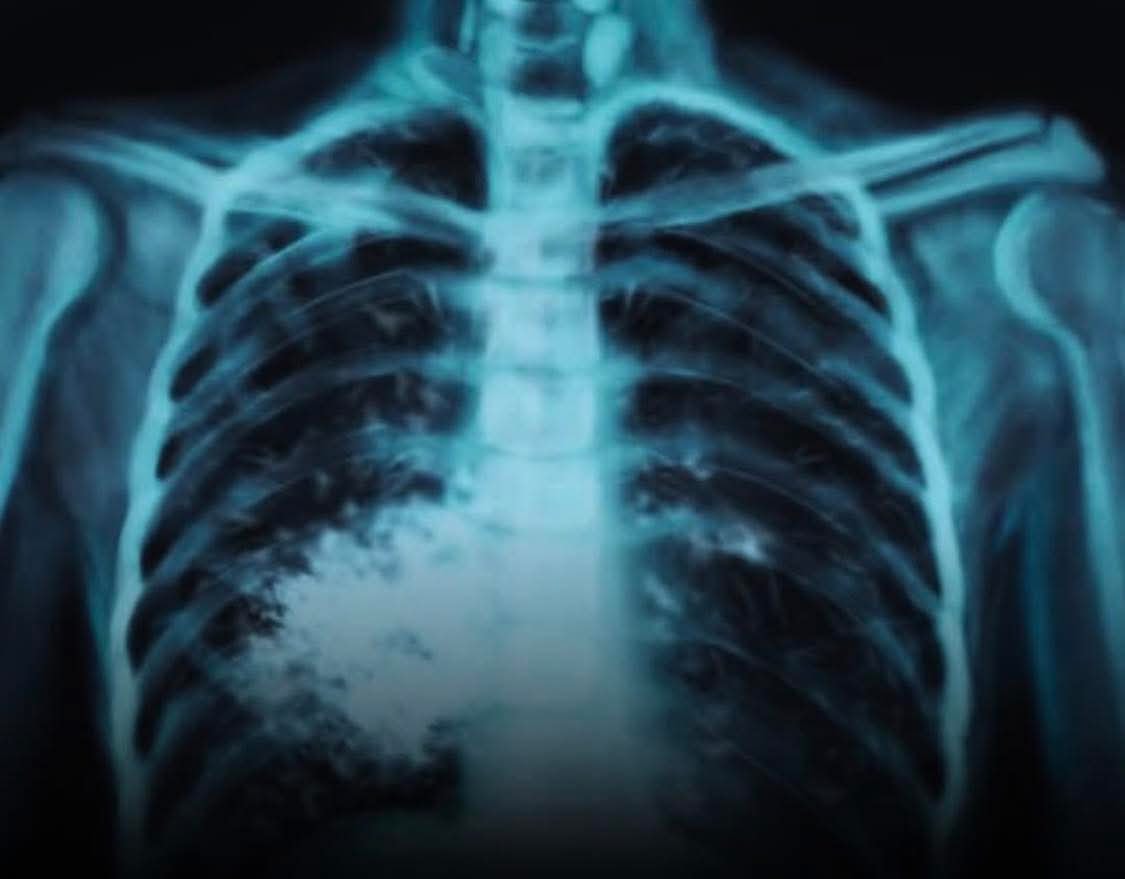

Oui, le vapotage est officiellement associé à des maladies pulmonaires graves et potentiellement irréversibles, comme la Maladie Pulmonaire Associée au Vapotage (MPAV) (EVALI aux USA), caractérisée par une inflammation aiguë, des lésions tissulaires, une toux, un essoufflement et nécessitant parfois une hospitalisation en soins intensifs. Bien que les effets à long terme ne soient pas encore totalement connus, l’inhalation des substances chimiques (comme le THC et l’acétate de vitamine E) peut causer des cicatrices permanentes dans les poumons et un rétrécissement des voies respiratoires, rendant le vapotage moins inoffensif que perçu, surtout pour les jeunes et les non-fumeurs.

MPAV (EVALI) : Une lésion pulmonaire sévère apparue en 2019, liée à des produits contenant du THC et/ou de l’acétate de vitamine E, pouvant être mortelle.

Lésions pulmonaires irréversibles : Des composants chimiques peuvent endommager les cellules pulmonaires et provoquer des cicatrices et un rétrécissement des bronches.

Symptômes fréquents : Toux chronique, essoufflement, respiration sifflante, production excessive de mucus.